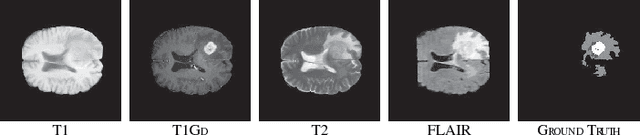

Abstract:Automatic extraction of liver and tumor from CT volumes is a challenging task due to their heterogeneous and diffusive shapes. Recently, 2D and 3D deep convolutional neural networks have become popular in medical image segmentation tasks because of the utilization of large labeled datasets to learn hierarchical features. However, 3D networks have some drawbacks due to their high cost on computational resources. In this paper, we propose a 3D hybrid residual attention-aware segmentation method, named RA-UNet, to precisely extract the liver volume of interests (VOI) and segment tumors from the liver VOI. The proposed network has a basic architecture as a 3D U-Net which extracts contextual information combining low-level feature maps with high-level ones. Attention modules are stacked so that the attention-aware features change adaptively as the network goes "very deep" and this is made possible by residual learning. This is the first work that an attention residual mechanism is used to process medical volumetric images. We evaluated our framework on the public MICCAI 2017 Liver Tumor Segmentation dataset and the 3DIRCADb dataset. The results show that our architecture outperforms other state-of-the-art methods. We also extend our RA-UNet to brain tumor segmentation on the BraTS2018 and BraTS2017 datasets, and the results indicate that RA-UNet achieves good performance on a brain tumor segmentation task as well.